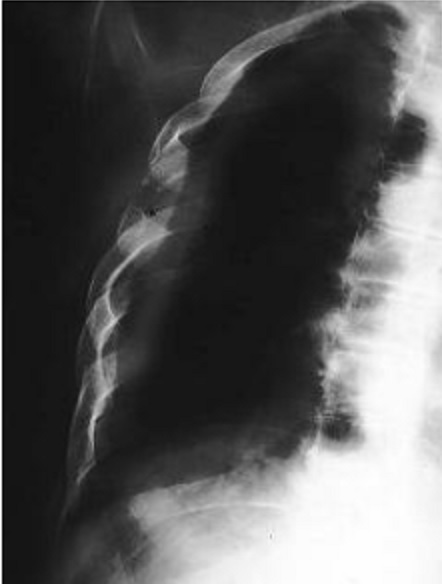

Image

radiologique standard PA pulmonaire de lyse costale

droit d'une lesion metastase costale |

Schéma du syndrome pariétal avec lésion osseuse. 1.

opacité en regard d'une ostéolyse costale ; 2. floue

en haut,

bien limitée en bas; 3 raccord

en pente douce |